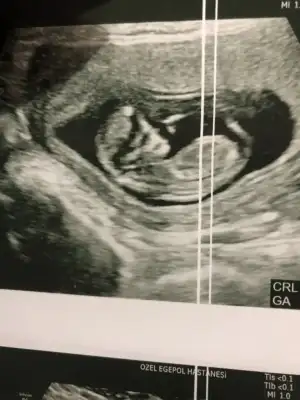

Canım bana erkeğe benziyor demiştin doktorda yüzde 60 erkek dedi. Buda son ultrason fotoğrafımız, burada 12+6 tekrar bakar mısın sana zahmet ?

20211217_152417.webp